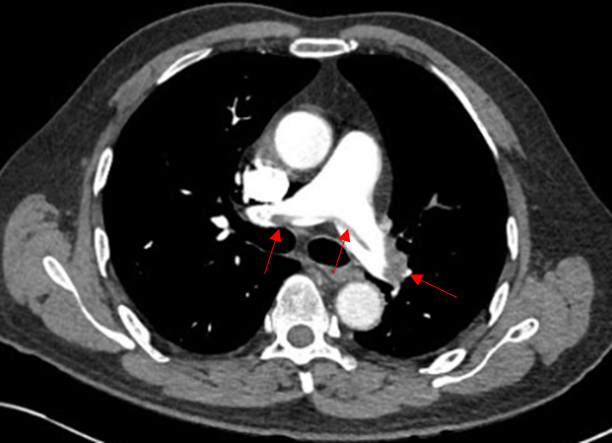

74세 여자가 1시간 전부터 가슴이 답답하고 숨쉬기가 힘들다고 한다. 7일 전 오른쪽 대퇴골절로 수술 후 입원 중이다. 10년 전부터 고혈압과 당뇨약을 복용 중이다. 혈압 140/70 mmHg, 맥박 110회/분, 호흡 32회/분, 체온 37.4℃이다. 호흡음은 규칙적이며 양쪽에서 균일하게 들린다. 혈액검사 결과는 다음과 같다. 가슴 컴퓨터단층촬영 사진이다. 치료는?

Img | CT: Thrombus at pulmonary artery |

• PTE가 의심되어 진행한 조영증강 흉부 CT에서 폐동맥에 혈전이 관찰되며, 이로써 PTE로 확진할 수 있다.